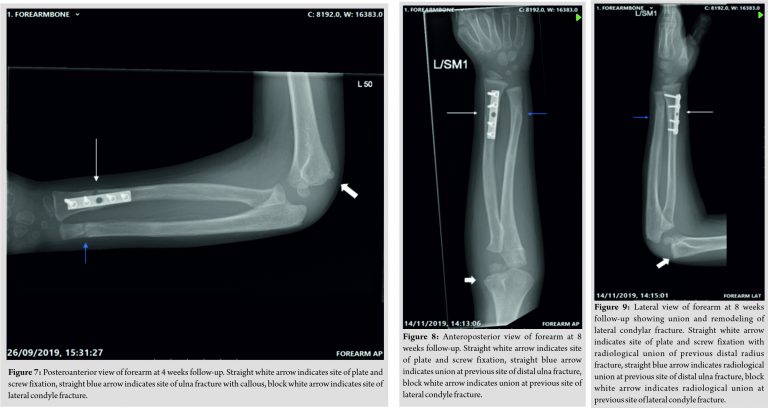

The child remained in an above elbow plaster cast for 4 weeks. On immediate removal of the plaster, elbow range of movement (ROM) was from 40 to 100°. A 80° of pronation was retained, but supination was restricted to 20°. No neurovascular deficit was identified and X-rays demonstrated good fracture union (Fig. 6, 7). At the 8 weeks post-operative follow-up, elbow ROM further improved, with almost full extension, 120° flexion, 70° of pronation and supination passively but achieving 90° actively on pronation and supination. By 12 weeks after surgery, there was a full ROM of the elbow, wrist, and forearm with complete radiological union (Fig. 8, 9). At 13 weeks post-injury, the plate was removed uneventfully and at 2 weeks after the procedure, his wound was well healed, and limb was neurovascularly intact with a full ROM of his elbow, wrist, and forearm at which point he was discharged from our care.